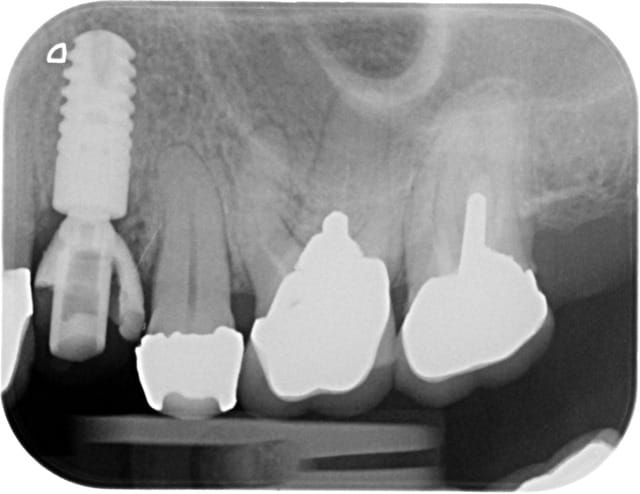

Alors j'ai commencé le traitement:

-ext 24 car mobilité type 2 + implant immédiat + couronne prov. en sous occ.

-Démontage difficile des ccm, mais surprise, traitement endo relativement mou et donc a priori pas trop délicat a reprendre.

-couronnes prov.

Évidemment tu as parfaitement raison c'est pourquoi lors de la confection des prov sur 13-23 je n'ai pas touché la racine pour adapter les prov. Ainsi lors de la chir , j'ai effectué une plastie vestibulaire radiculaire qui a permis de déplacer coronairement la limite prothetique de 2 mm env..

Ainsi j'ai pu effectué classiquement un conj enf.conjointement a un allongement de couronne de 12 à 22.